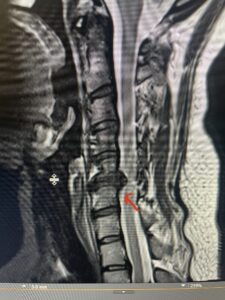

This 47-year-old male who four months prior was lifting weights developed sharp pain in his neck. After that he developed progressive numbness in his arms, neck pain and headache. He said that the right arm was worse than the left. On examination the patient had long tract weakness on the right side which included his triceps, finger extensors, hip flexors, and dorsiflexors. The patient did not have hyperreflexia. MRI (Fig. 2) demonstrated a massive, extruded disc herniation with severe cord compression. The patient because of progressive myelopathy and spinal cord compression was indicated for anterior cervical discectomy and fusion at C4-5 (Fig. 3). Patient had significant improvement of weakness and numbness post operatively.

Fig. 2a Sagittal T2-weighted cervical MRI demonstrating large C4-5 herniated disc with spinal cord compression (red arrow)